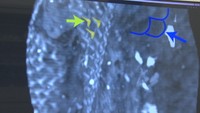

人魚のミイラに「哺乳類とも魚類とも異なる特徴」 研究チームが中間報告 岡山

生物学が専門の、倉敷芸術科学大学・加藤敬史教授